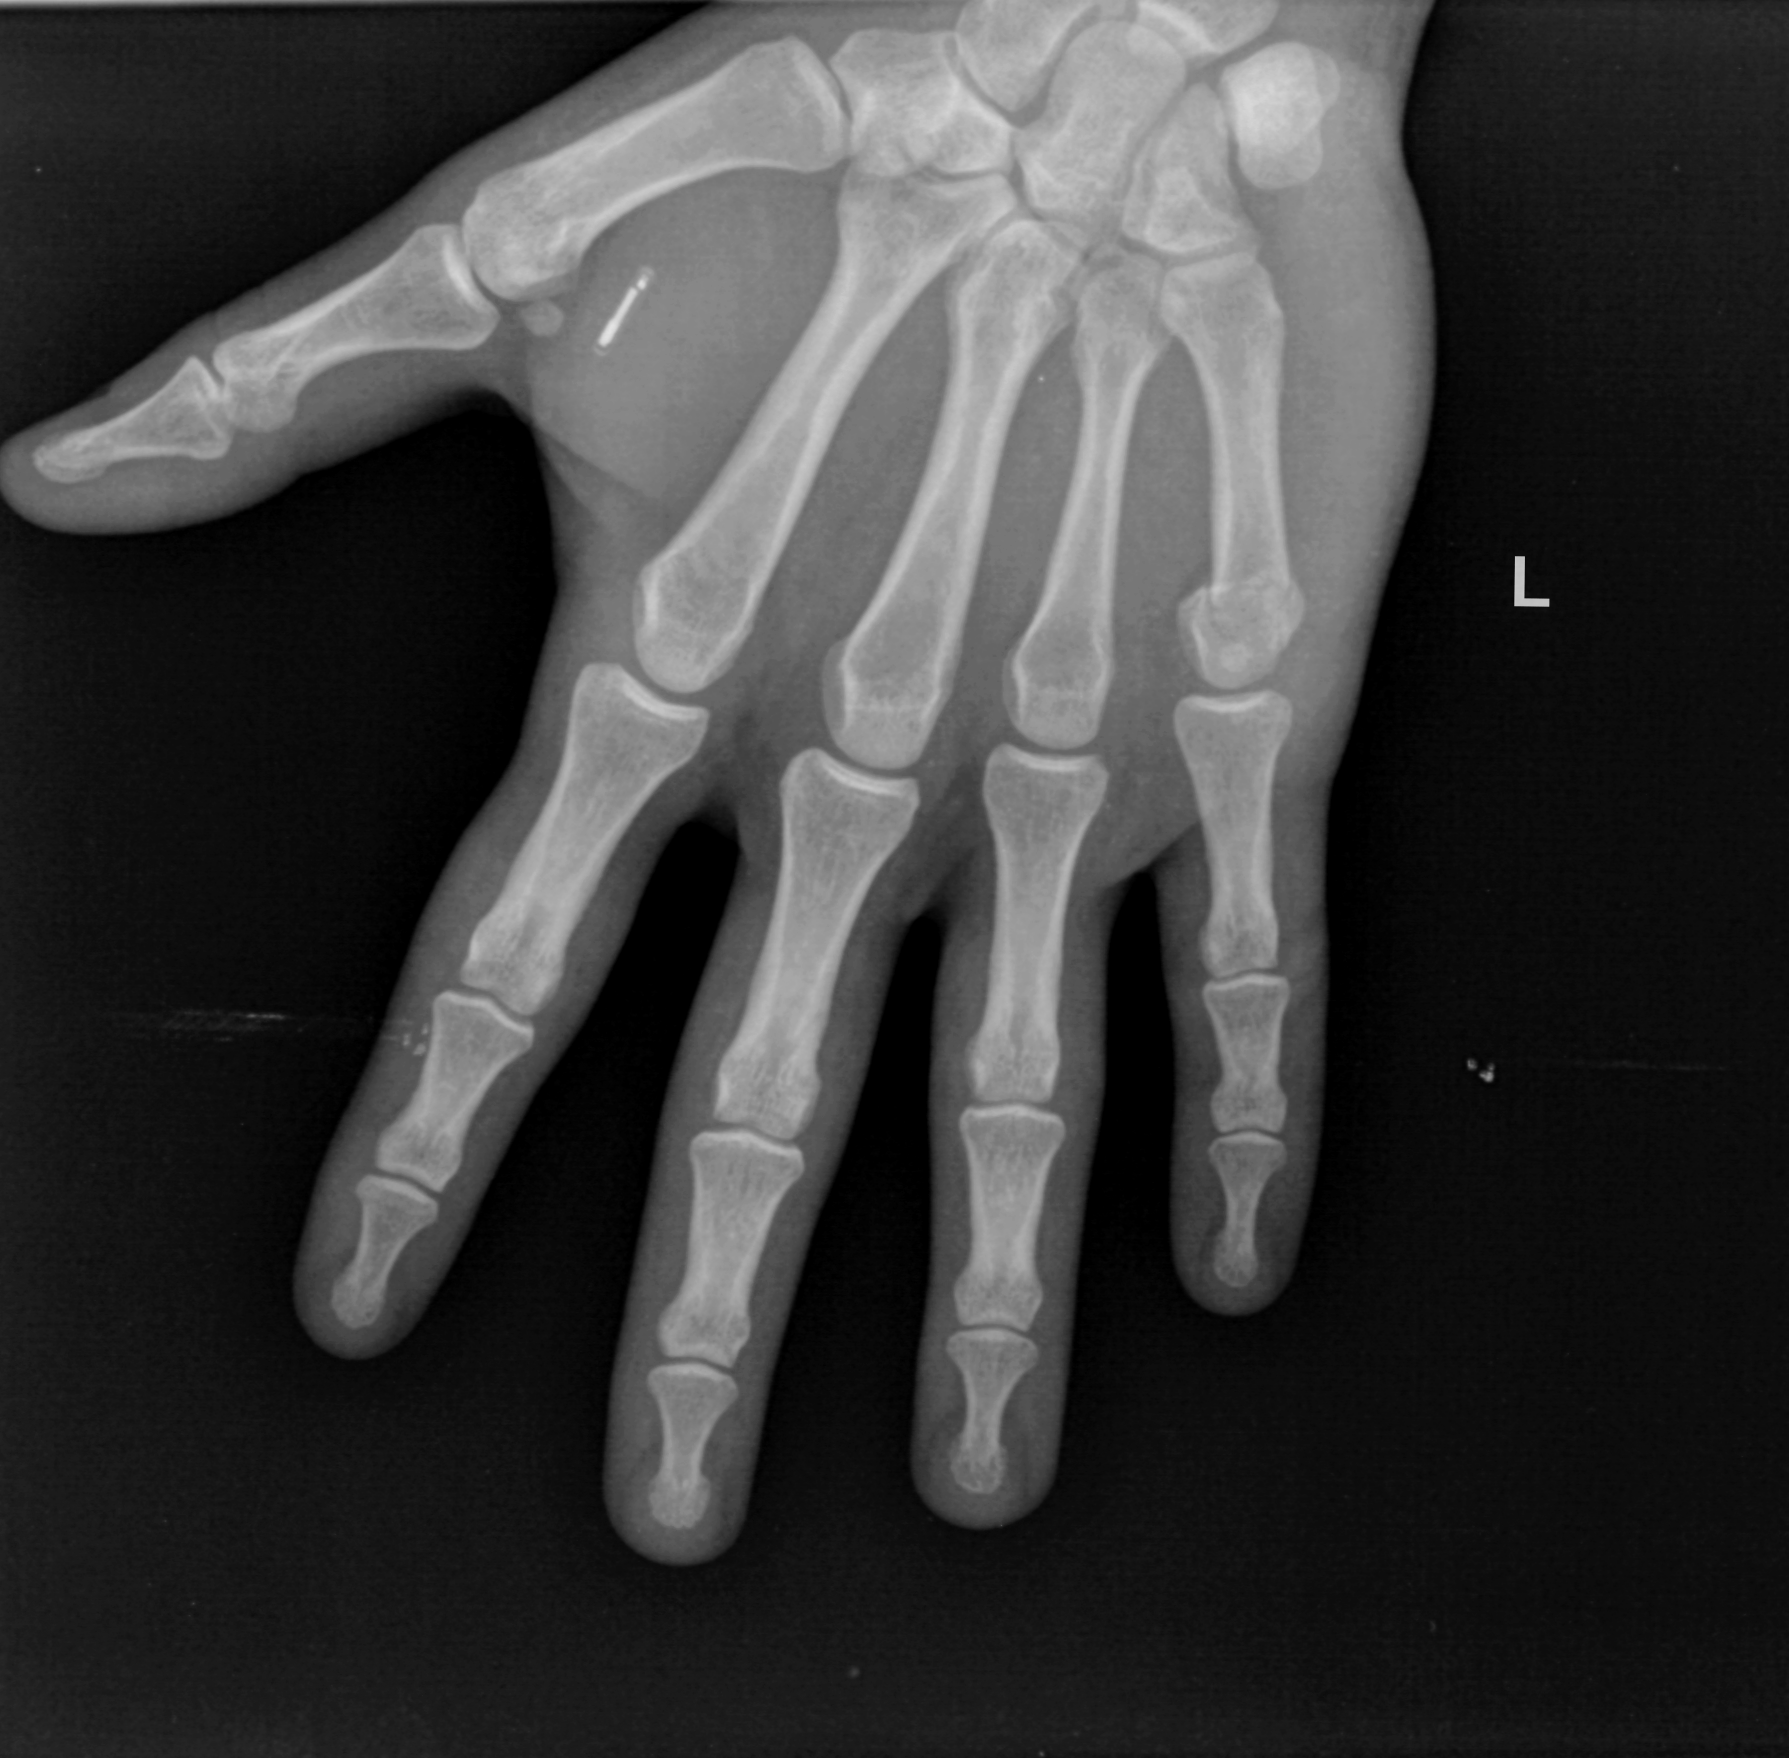

I got an NFC chip installed in my left hand. The Biohacking Village at DEF CON 25 was offering implants to the first 45 eligible people — eligible meaning sober and over 18. Ol’ Jon got lucky number 45. It feels weird to know I can read and write data to my body.

The implant was the xNT NFC Tag by Dangerous Things, installed by a gentleman who goes by the name of Cooper.